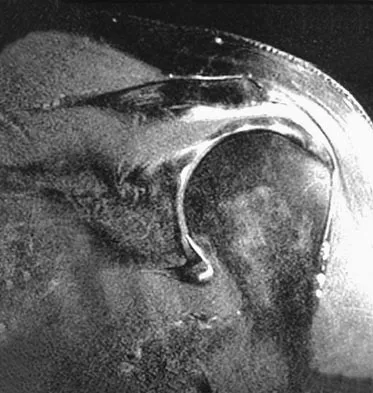

A 21-year-old hockey player who has recurrent shoulder subluxations undergoes an anterior capsulorrhaphy under general anesthesia, and an interscalene block is used to relieve postoperative pain. At the 1-week follow-up examination, he reports loss of sensation over the lateral region of the shoulder and is unable to actively contract the deltoid muscle. The remainder of the examination is normal. What is the best course of action at this time?

Explanation